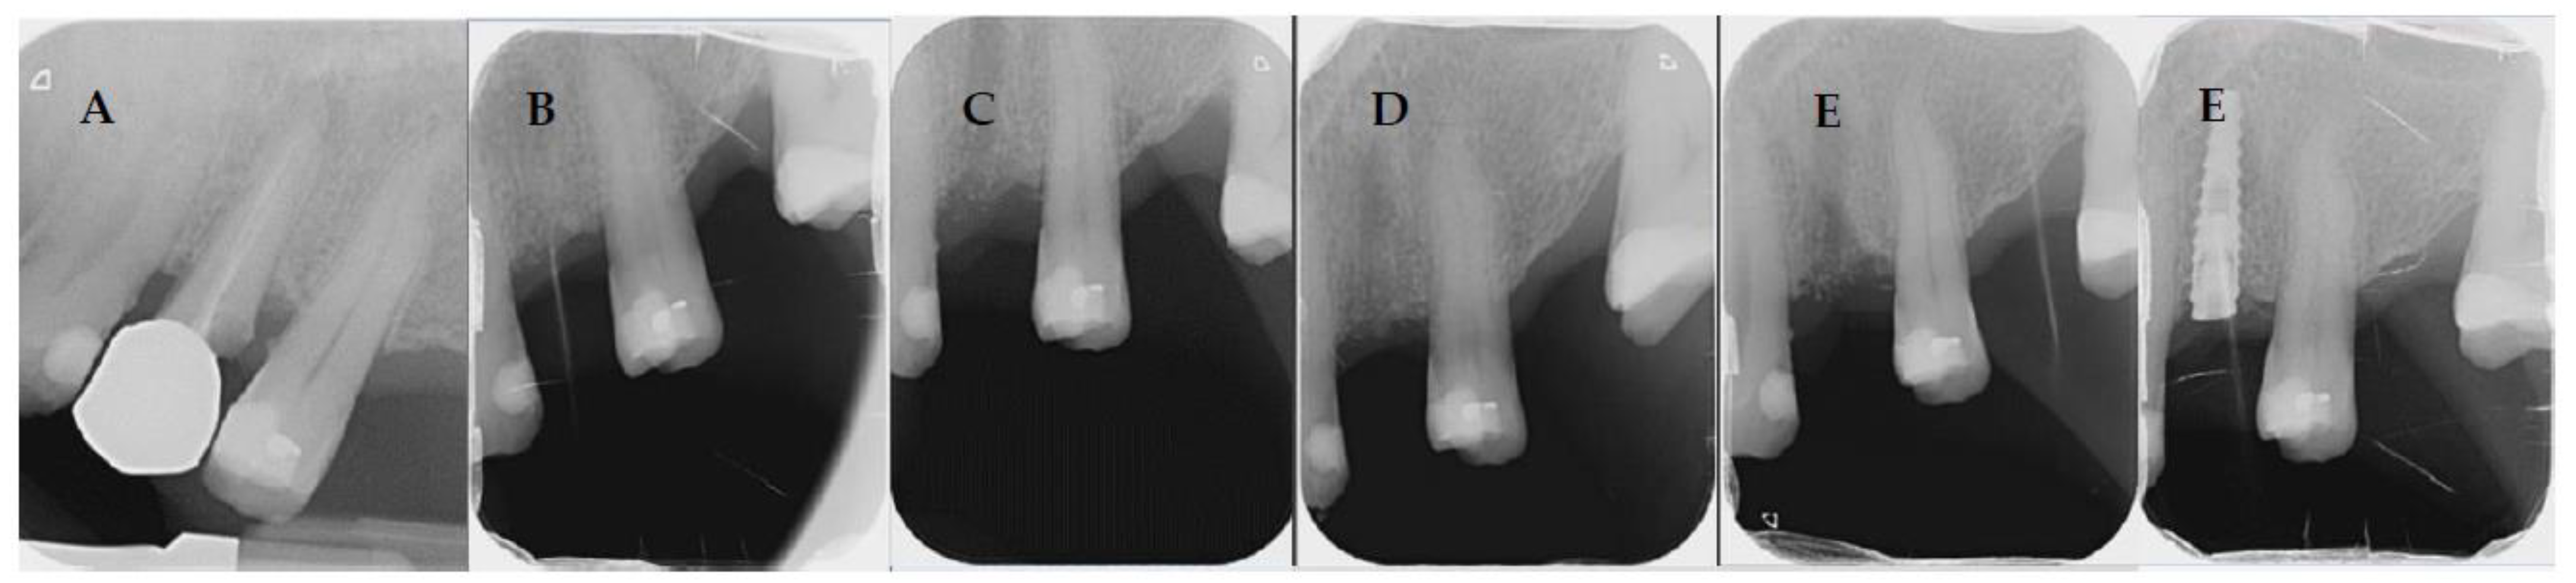

4.1. Patient No. 1

4.2. Patient No. 2

4.3. Patient No. 3

4.4. Patient No.4

4.5. Patient No.5

4.6. Patient No.6